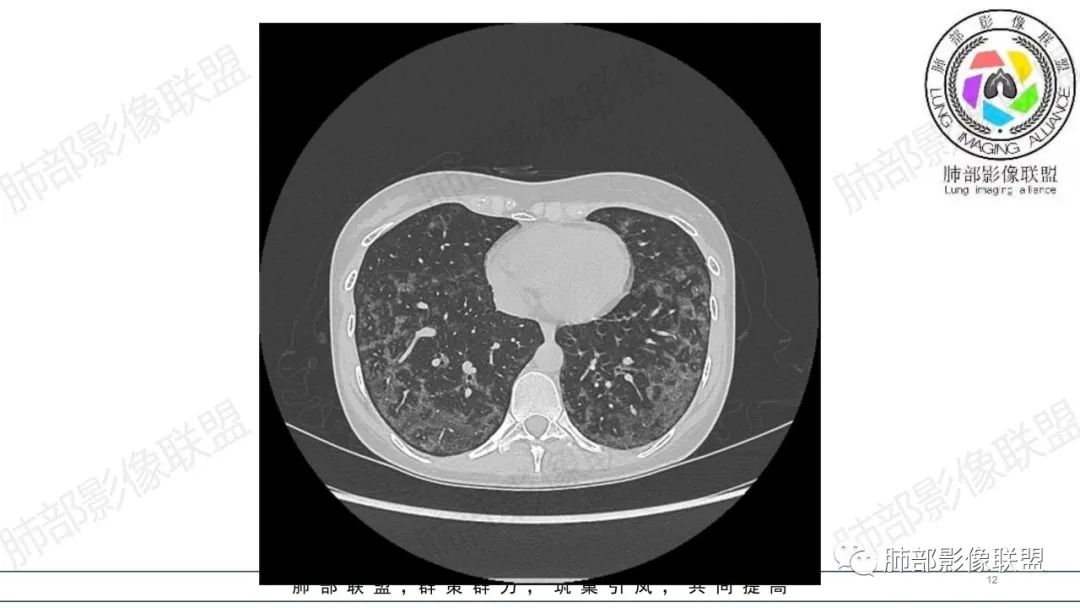

34岁女性患者,“哮喘”病史30年,近期有可疑刺激性气体吸入史;因乏力半年,咳嗽、憋气、发热4天就诊;6.1CT提示双肺广泛毛玻璃影及粟粒样结节,胸膜下闲置及血管周闲置,可见树丫征,部分小叶间隔增厚。考虑:1.过敏性肺泡炎,有可疑刺激气体接触史,胸膜下闲置,广泛毛玻璃影,地图样分布,粟粒结节边界模糊,支持过敏性肺泡炎,但糖皮激素治疗效果不佳,且动态复查血常规血红蛋白进行性降低,过敏性肺泡炎 不符合;2.肺含铁血黄素沉积症:患者30“哮喘”病史,可能为肺含铁症状,肺部CT提示双肺弥漫毛玻璃影及粟粒结节影,中下肺明显,肺底部分小叶间隔增厚,近期咳嗽、憋气、发热,血常规血红蛋白进行性下降,考虑肺含铁急性期症状,但临床无咯血症状,肺含铁不典型。综合考虑:肺含铁血黄素沉积症>过敏性肺泡炎。

年轻女性 ,急性喘息发热,肺部影像弥漫磨玻璃密度,部分细小腺泡结节,胸膜下黑线显示,短期复查,病变密度增高,下肺明显,血管周围肺组织累及较少、且逐渐成小叶间隔分布。考虑弥漫肺泡内病变,并经淋巴道转移,下肺比上肺明显,多为免疫细胞功能下肺较强。1.过敏性肺泡炎,有相关病史,三层密度特点、头尾测分布,符合。2 肺泡微石症,多有钙化,且缓慢起病,病程不太符合,放待排。3 吸入相关肺损伤,有病史,疾病演变过程也符合渗出-肉芽肿改变,建议详细询问病史。4 感染性病变,结核?病变气道分布为主,如此弥漫且没有树丫不符合。5.巨细胞病毒,可以磨玻璃 结节 改变,没有免疫缺陷病史。最后考虑吸入所致 1过敏性肺泡炎、吸入性肺损伤 鉴别肺泡微石症。